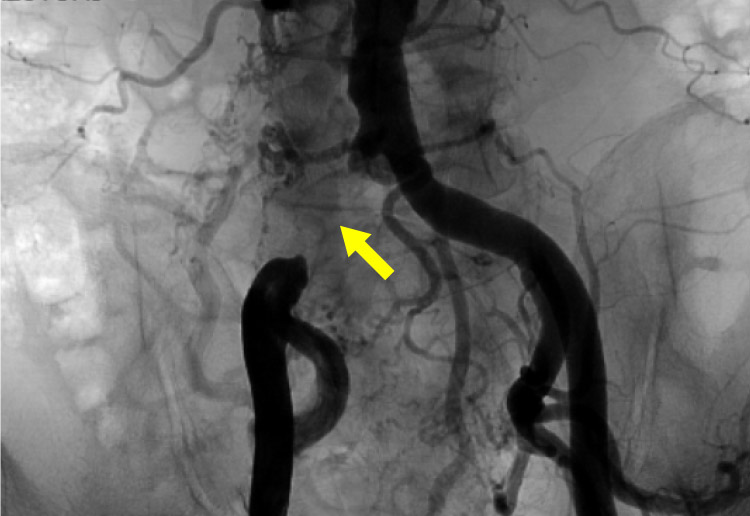

経皮的血管形成術(EVT)

狭くなった血管や詰まった血管に対して、カテーテルを使い、バルーンで拡張したり、ステント(金属の筒)を留置する治療を行います。石灰化が高度な病変には、バルーンだけでは拡張しにくいため、CROSSER(振動で石灰化を軟らかくする器具)を用いて治療することがあります。

閉塞している血管に対してワイヤーを通過させバルーン拡張し最終的にステントを留置し血管を拡げ、血流を改善します。